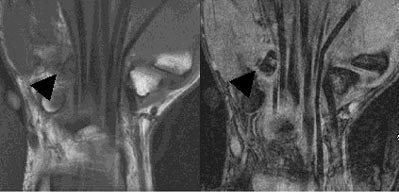

| Coronal MR images illustrate the difficulty in visualizing fractures of the hook of the hamate. These fractures (black arrows) are in the coronal plane, and are therefore difficult to visualize on both the T1-weighted (right) and gradient echo (left) images. Images courtesy of Dr. Douglas P. Beall. |